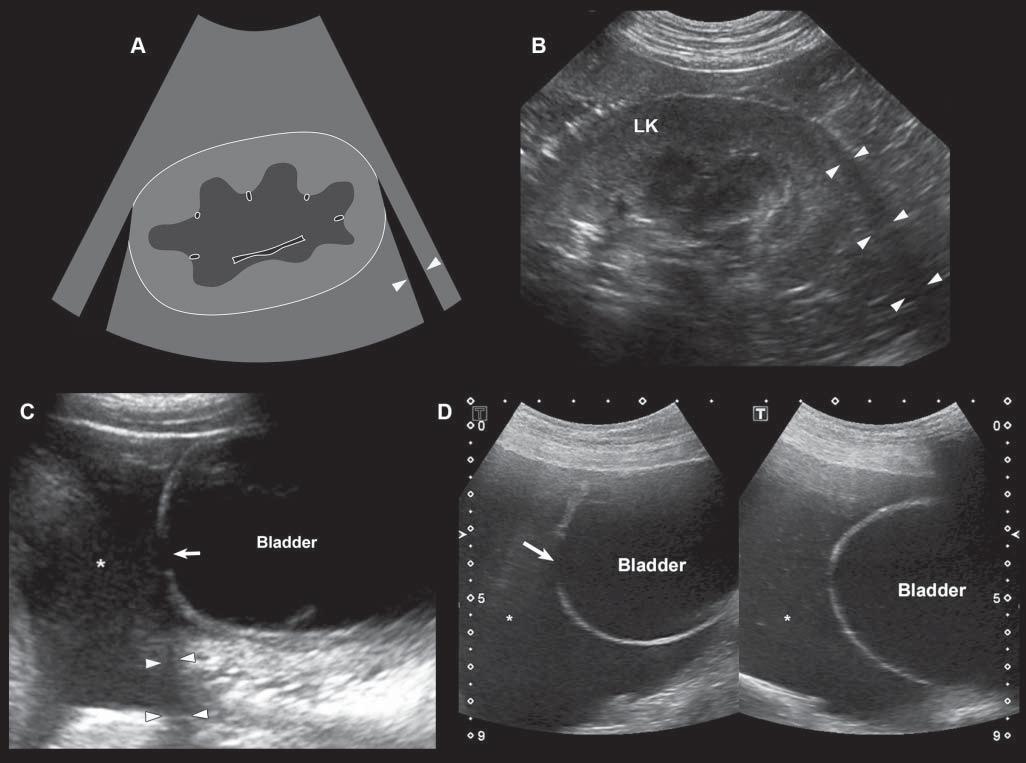

Edgeshadowing appearsasdiscrete,triangular zonesoflowamplitude,attheedgeofacurved structure(Figure1.14A).When,thecurvedstructure isfluidfilled,theedgeshadowingartifactbordersthe enhancementartifact.Thistypeofrefractiveshadowingcanbeconfusing,especiallywhenitoccursatthe

cranialaspectofafluidfilledbladder,andappearsas a“defect”ofthewall(Figure1.14B).

Figure1.14. Edgeshadowingandrefraction.A,B: Edgeshadowing(arrowheads)isoftenseeninprolongationoftherenal pole.LK,leftkidney. C: Thecurvatureofthebladderwallcausesbeamrefraction,whichresultsinanacousticshadow(arrowheads)inthisdogwithechogenicperitonealeffusion(*).Aholeinthebladderwall(arrow)isartifactuallycreated. D: Inanother dogwithcardiactamponadeandmarkedperitonealeffusion(*),theartifactualholeinthebladderwall(arrow)isattenuated byrepositioningthetransducerwithadifferentangulation.